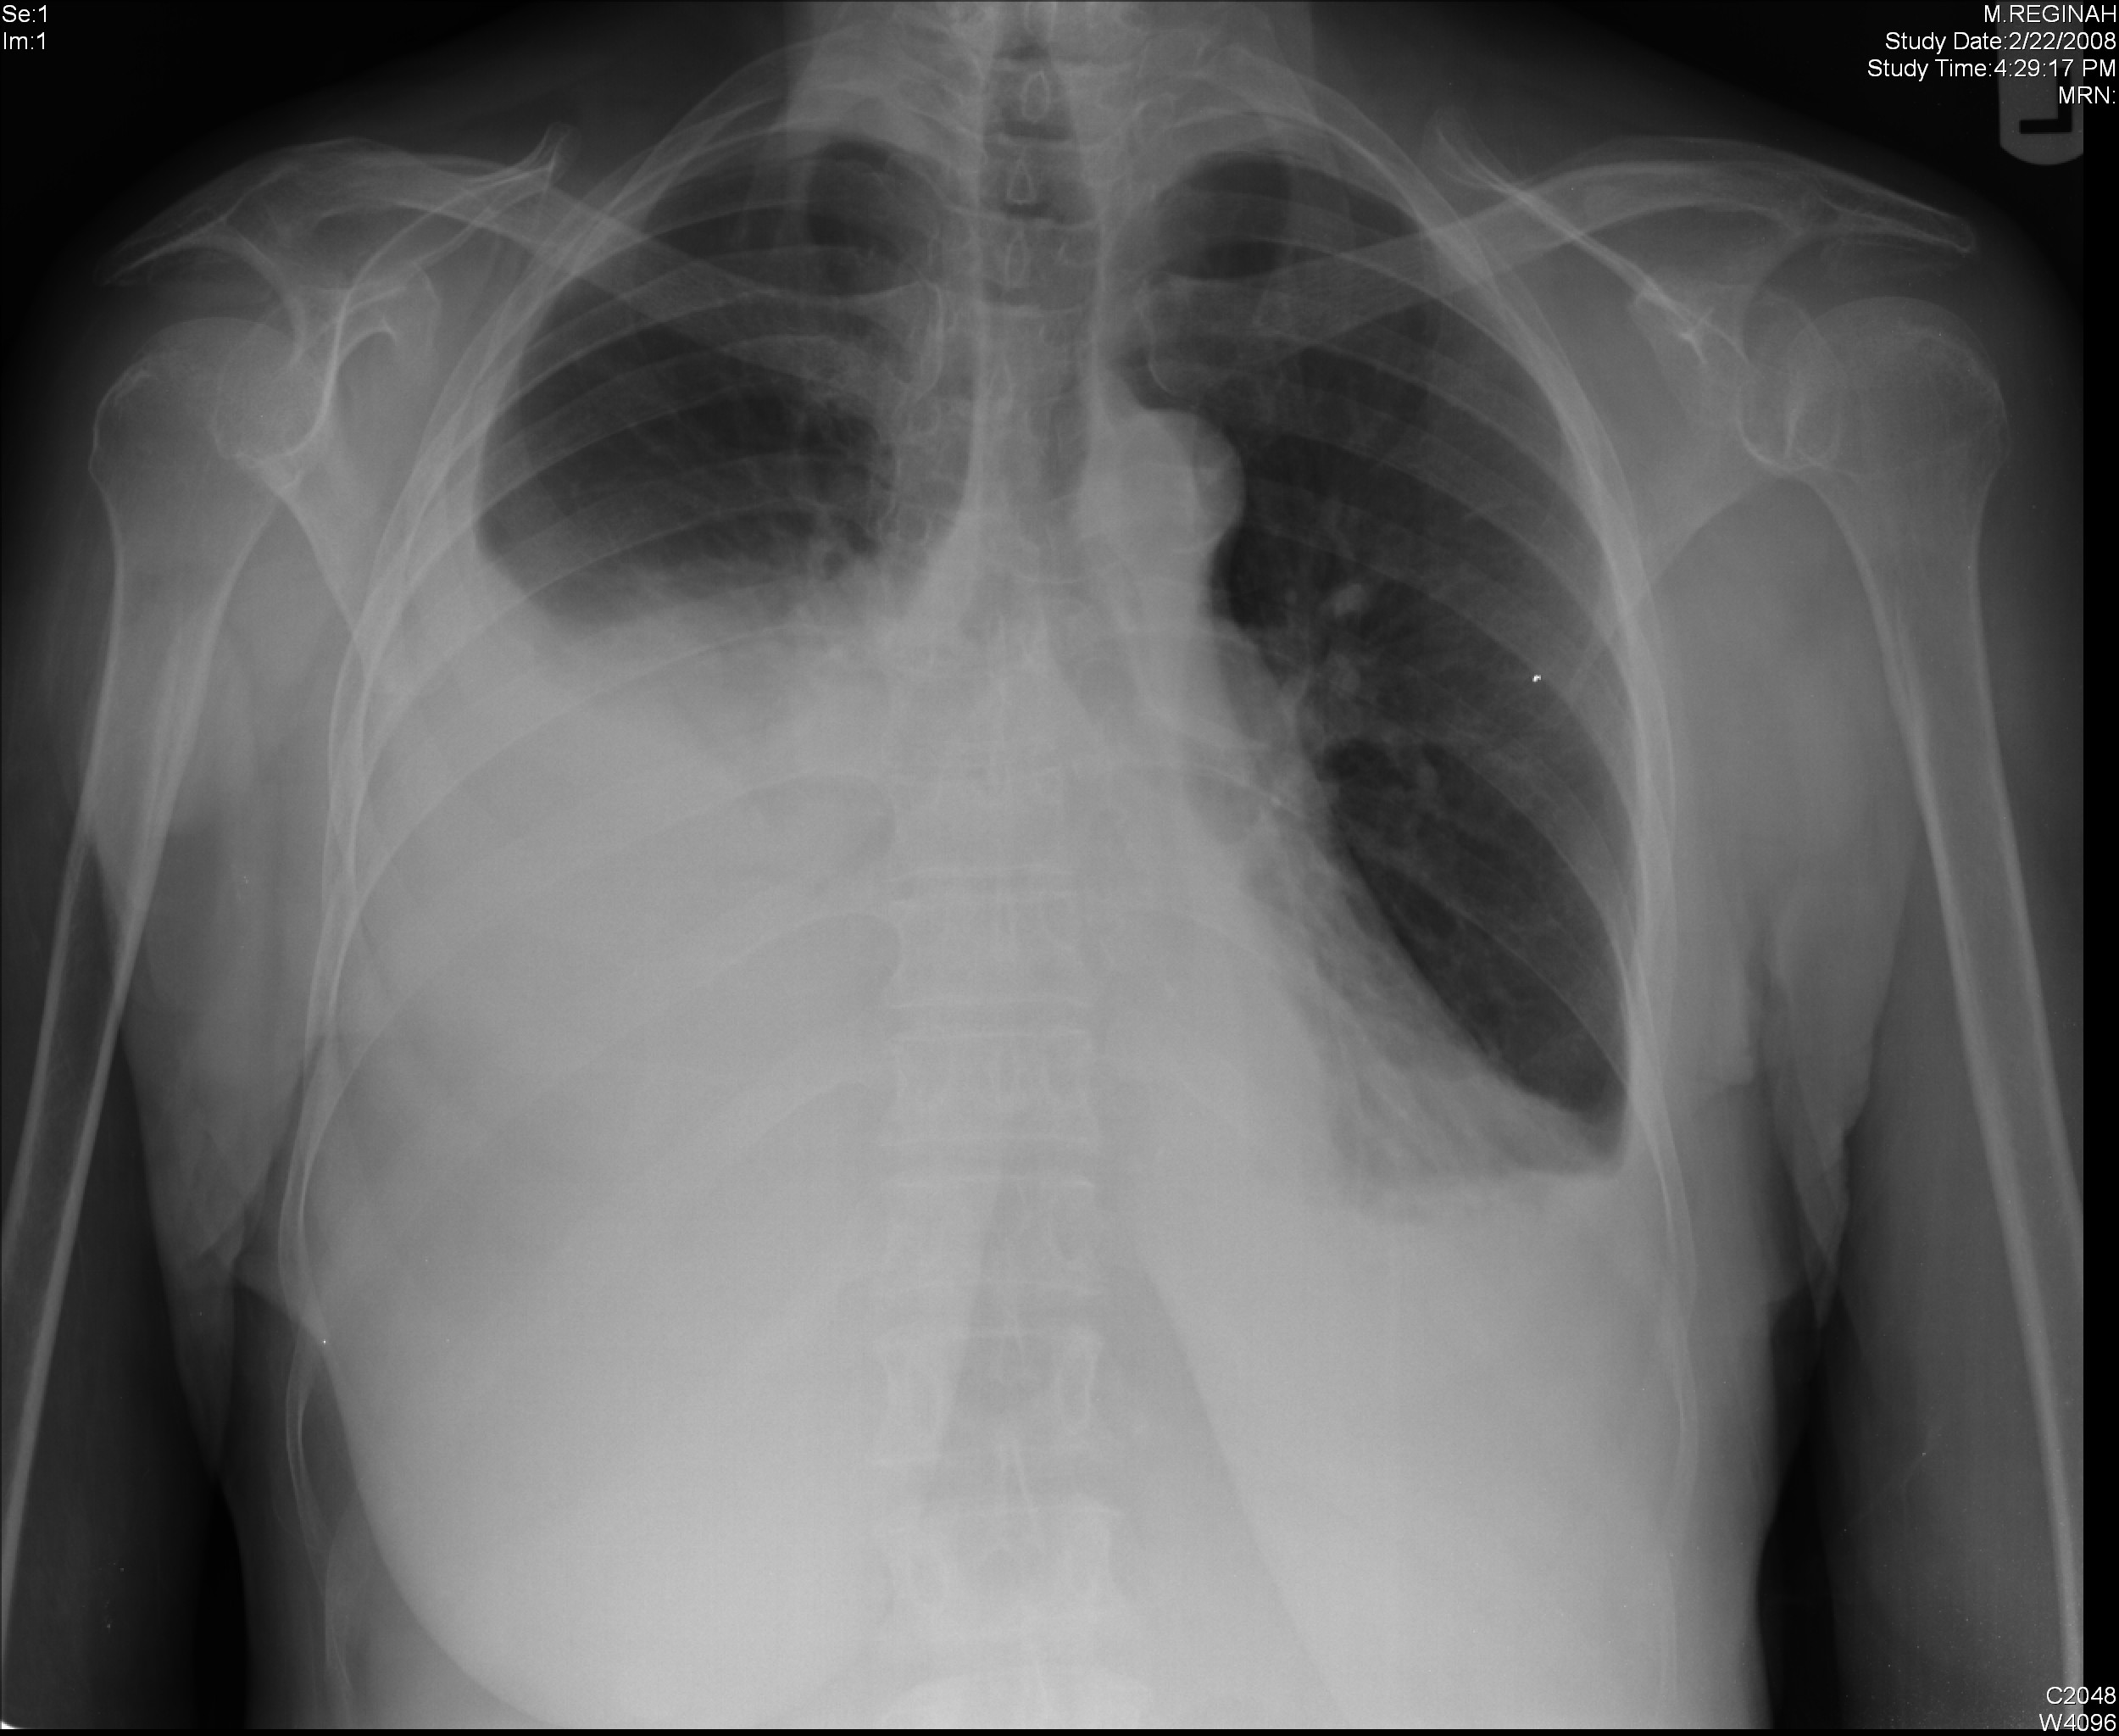

흉막 삼출 증상 및 원인, 치료

흉막 삼출은 폐와 흉강 사이의 공간에 체액

축적되는 것을 말합니다. 폐렴 및 기타 여러

질환으로 인해 발생할 수 있으며 생명을

위협할 수도 있습니다

흉막 삼출이란?

사람이 흉막 삼출이 있을 때, 그것은 액체가 폐와

흉강, 또는 흉강 사이의 공간에 모였다는 것을

의미합니다